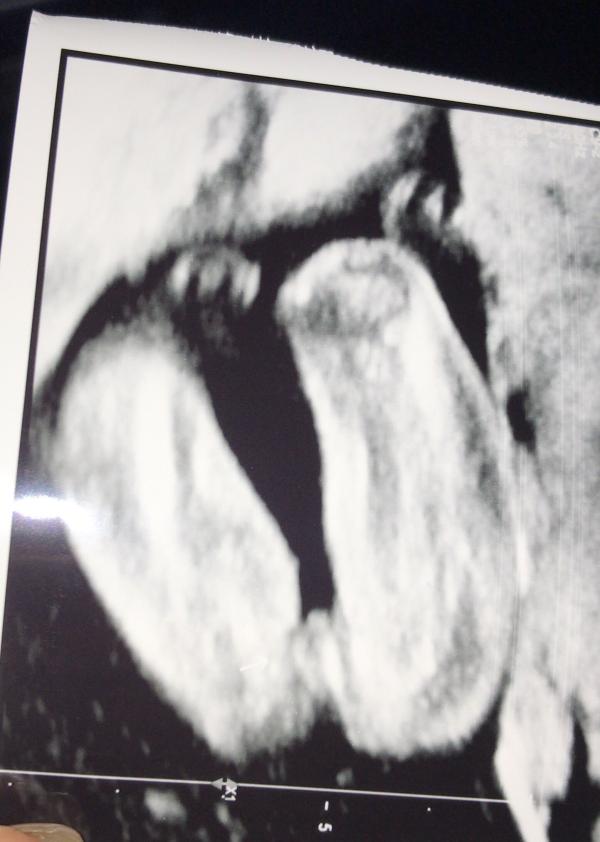

На узи 20 недель сказали 99,9 % девочка 👧🏻😭

Я ревела от счастья и не верила ( на самом деле до сих пор не уверена и записалась на еще одно узи )

Очень быстро посмотрели пол и я чем больше смотрю на снимок ,тем больше накручиваю что там писюньчик 😂😅

Поздравляю. По снимку думаю, что все таки девочка. У нас так же все выглядело на УЗИ. Но для меня будет большим сюрпризом, если родится мальчик, так как все готово к девочке)